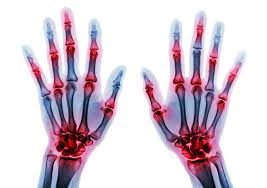

Hand- en polstrauma’s komen vaak voor en kunnen uiteenlopen van een simpele kneuzing tot een complexe breuk. Als doktersassistent is het cruciaal om snel de juiste inschatting te maken. In deze webinar leer je hoe je met vertrouwen triageert en letsels onderzoekt.